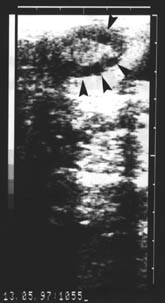

The study was performed out on ten Holstein cows, of unknown reproduction history, 3 to 7 years old, from the clinical depot PIK Vrbovec d.d. On the afternoon before slaughter the cows were thoroughly examined gynaecologically - vaginally, by rectal palpation, and then by ultrasound using an Aloca Echo Camera SSD-210 DX II device with the transrectal linear 5 MHz transducer. The echograms of each ovary were printed out on a Mitsubishi Video Copy AP-8600 printer, Japan (Fig. 1). The next morning the cows were slaughtered and their ovaries were removed within a maximum period of 30 minutes after slaughter. The ovaries were transported to a laboratory in a thermos of Ringer solution and antibiotic addition (100 I.U. penicillin and 100 µg streptomycin/ml) at temperature of 30 oC. After arrival at the laboratory the ovaries were washed in the Ringer solution, warmed to a temperature of 37 oC. All the forms on the ovaries were macroscopically described and the results compared with the rectal and ultrasound finds of each cow determined on the previous day (Fig. 2). The contents of follicles (diameter more than2 mm) visible at the ovarian surface were aspirated with a 5 ml syringe and an 18-gauge needle (outer diameter 1.2 mm) and placed in Ringer/antibiotic solution, warmed to 37 oC. Follicular contents were viewed under stereomicroscope, magnification ×15, ×100, ×210.

Fig. 1. Echogram of the cow ovary in follicular phase. Arrows mark follicles.

Fig. 2. Macroscopical image of the cow ovary shown in Fig. 1, 24 hours following the ultrasound examination. Arrows mark follicles.